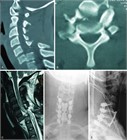

1. CT、MRI:MRIは脊椎と脊髄の同時評価が可能であり有用性が高い。しかし撮像時間を有するならCTを優先させる(推奨度1)